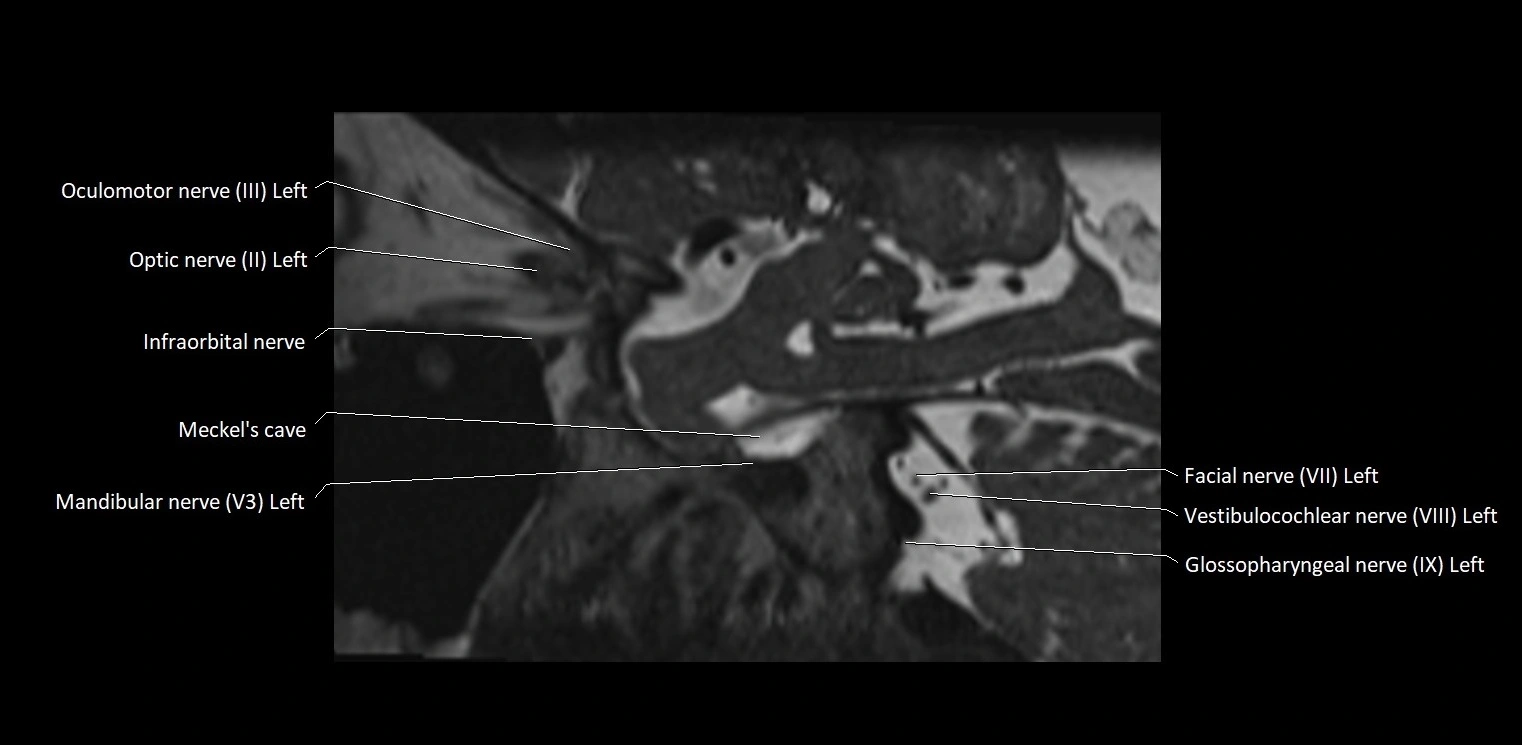

MRI Appearance

• The abducens nerve is a small, thin, linear structure

• Best visualized on high-resolution T2-weighted 3D MRI sequences (e.g., FIESTA or CISS)

• Seen as a hypointense (dark) line running from the brainstem at the pontomedullary junction, traversing the prepontine cistern, and entering Dorello’s canal under the petrosphenoidal ligament, then into the cavernous sinus, and finally the orbit

• May be challenging to visualize in standard MRI due to its small size

• Pathology may be inferred by absence, displacement, or enhancement of the nerve

MRI images

image